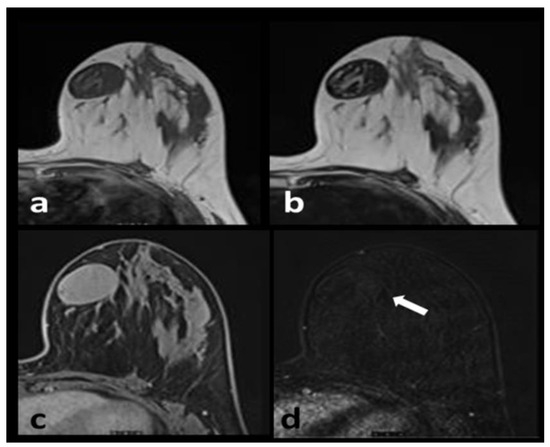

Phyllodes tumors